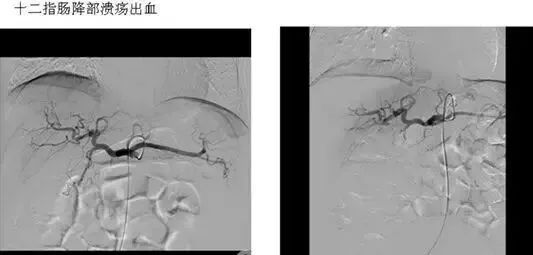

(1)血管收缩治疗 经导管向有关动脉内滴注加压素,以控制胃肠道出血,例如食道胃静脉曲张出血、胃粘膜弥漫性出血及结肠憩室出血等等。

(5)应用栓塞术或血管加压素治疗胃肠道血管出血。